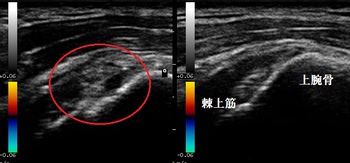

右棘上筋 超音波長軸像 左同部(健側)

鶴ヶ島市若葉 40代男性会社員。 肩の痛み、右腱板断裂、交通事故。

2週間ほど経過していましたが、右腕が上げづらく傷みもありました。当接骨院で超音波検査を

実施したところ、右棘上筋の断裂が認められました。

超音波検査を行ったところ、右棘上筋が部分的に断裂し、肩峰下滑液包に炎症が起きている様子が

認められました(左画像の赤丸の中)。